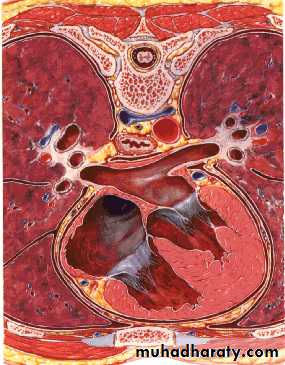

Cross sectionCAT image

head

ComparisonsCross section

CAT image